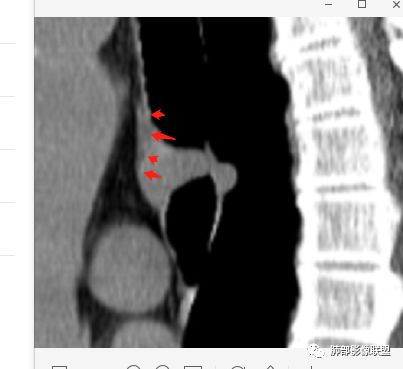

南边:

南边:高密度软骨在这两点上停了

南边:挤过去了,说明是从软骨间过去的

尘缘:@Shelia,部分是向前推,部分是向后推的。这个地方应该还有向后推的;肿物是从向前推与向后推这个间隙跨软骨的。